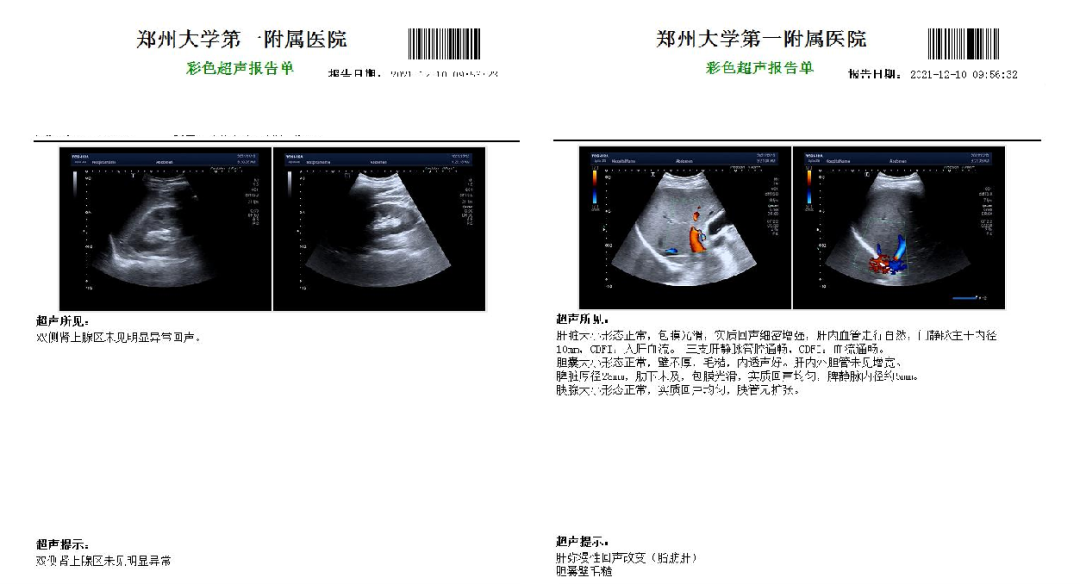

超声检查:

CTP:

高密度脂蛋白、同型半胱氨酸、叶酸异常

血常规、肝肾功能正常

ECG正常